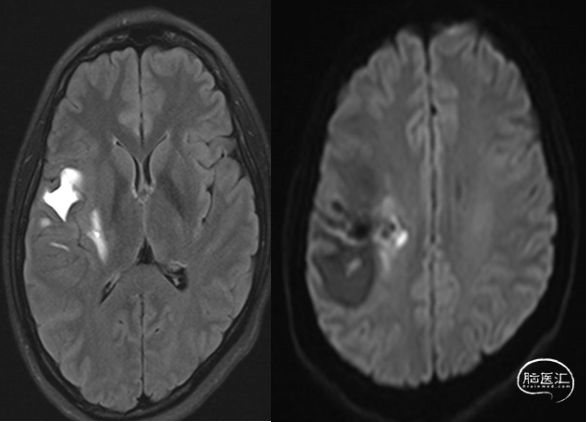

10个月DSA复查

静脉入路超选

供血动脉球囊保护;静脉压力锅技术,onyx18栓塞

术后即刻造影血管畸形消失